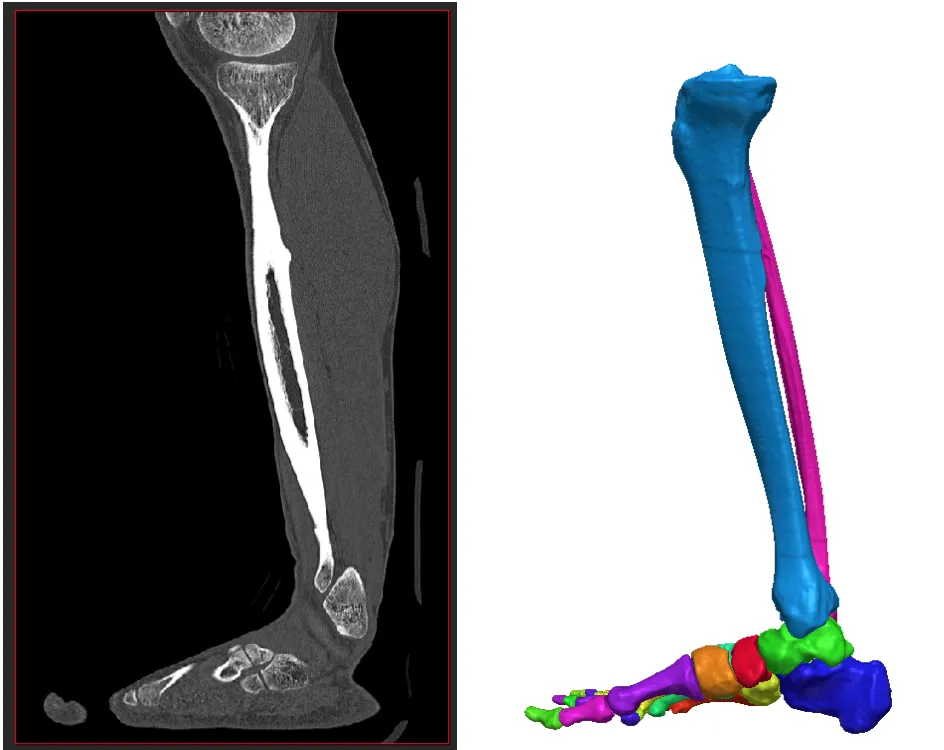

不同于依赖几何学、群体化或通用方法的传统途径,其突破性的理念在于:基于患者影像为每个人创建虚拟的个性化足部模型,并利用逼真的仿真技术来确定最佳治疗方案。

- 其二是个性化手术仿真平台,协助骨科医生基于清晰的病因分析制定手术计划,该平台还提供患者影像分析和分割工具。

Digital Orthopaedics 致力于保障全民各年龄段的健康与福祉,并推动建设有韧性的基础设施,促进可持续工业化,推动创新发展。他们的目标是改变并优化骨科手术中患者的医疗保健体验。3DOXpert 提供融合最佳实践与仿真技术的专业化服务,是全科医生或专科临床医生的理想助手。医生可以为患者的足部生成数字孪生,从而真实地呈现病理情况,并更好地规划手术方案。

Digital Orthopaedics 是一家数字健康初创公司,正通过个性化、仿真驱动的治疗规划来变革骨科医疗。该公司通过医学影像创建患者足部与踝部的虚拟三维模型,使外科医生能够模拟手术过程、预测手术结果,并根据个体的解剖结构与功能需求制定个性化干预方案。